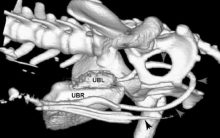

Subcutaneous Ureteric Bypass or SUB placement in Cats

Subcutaneous Ureteric Bypass or "SUB" placement By Tim Charlesworth Ureteric obstruction is an increasingly diagnosed condition in cats with ...